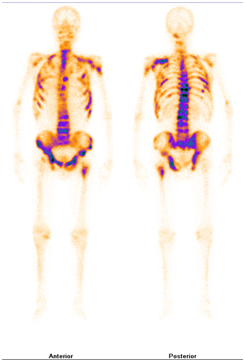

肿瘤骨转移与放射性核素骨扫描